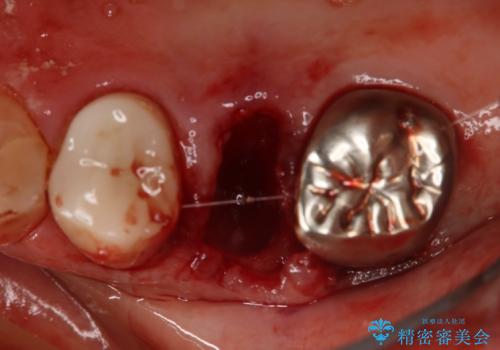

- 右上小臼歯の破折を理由に来院された患者様です。

残根状態で保存不可能と判断し、抜歯した上で補綴することを提案しました。

抜歯と同時にインプラントを埋入することで治療の期間・回数を減らし、患者様への負担を大幅に軽減することができます。

今回の患者様においては、術後に痛みは発生せず良好な経過を得ることが出来ました。